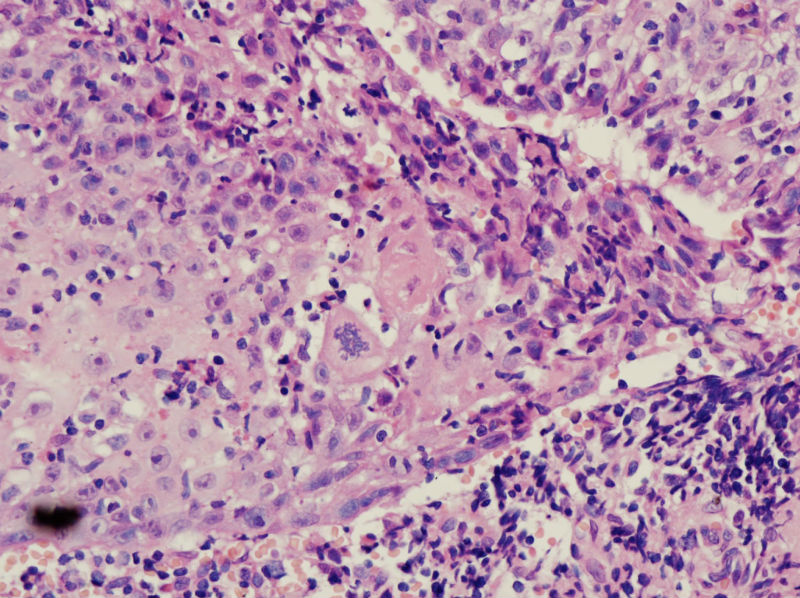

男,45岁,上唇菜花样肿物,请老师指教

图1